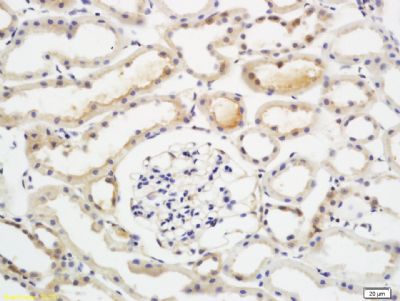

Paraformaldehyde-fixed, paraffin embedded (rat kidney tissue); Antigen retrieval by boiling in sodium citrate buffer (pH6.0) for 15min; Block endogenous peroxidase by 3% hydrogen peroxide for 20 minutes; Blocking buffer (normal goat serum) at 37°C for 30min; Antibody incubation with (EIF2AK2) Polyclonal Antibody, Unconjugated (bs-1493R) at 1:200 overnight at 4°C, followed by a conjugated secondary (sp-0023) for 20 minutes and DAB staining.

Tissue/cell: rat kidney tissue; 4% Paraformaldehyde-fixed and paraffin-embedded;

Antigen retrieval: citrate buffer ( 0.01M, pH 6.0 ), Boiling bathing for 15min; Block endogenous peroxidase by 3% Hydrogen peroxide for 30min; Blocking buffer (normal goat serum,C-0005) at 37℃ for 20 min;

Incubation: Anti-EIF2AK2/PKR Polyclonal Antibody, Unconjugated(bs-1493R) 1:200, overnight at 4°C, followed by conjugation to the secondary antibody(SP-0023) and DAB(C-0010) staining